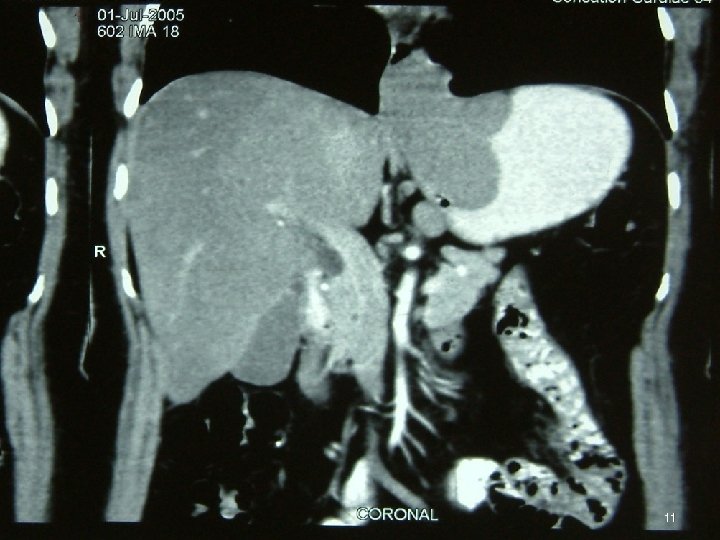

Investigations • • • Chest X Ray USG CECT EUS Ba Swallow 3

Diagnosis • FDG PET = mandatory ►FDG-PET CT scan is ideal • MD-CE-CT = image modality of choice for abdomen (if FDG-PET-CT is not available) • MR • Evaluate by Chol or RECIST criterion 46

Diagnosis • Polyp / Metastases of Lobular Breast CA in Ut • GIST, Lymphoma / 2 nd primary at GI jn